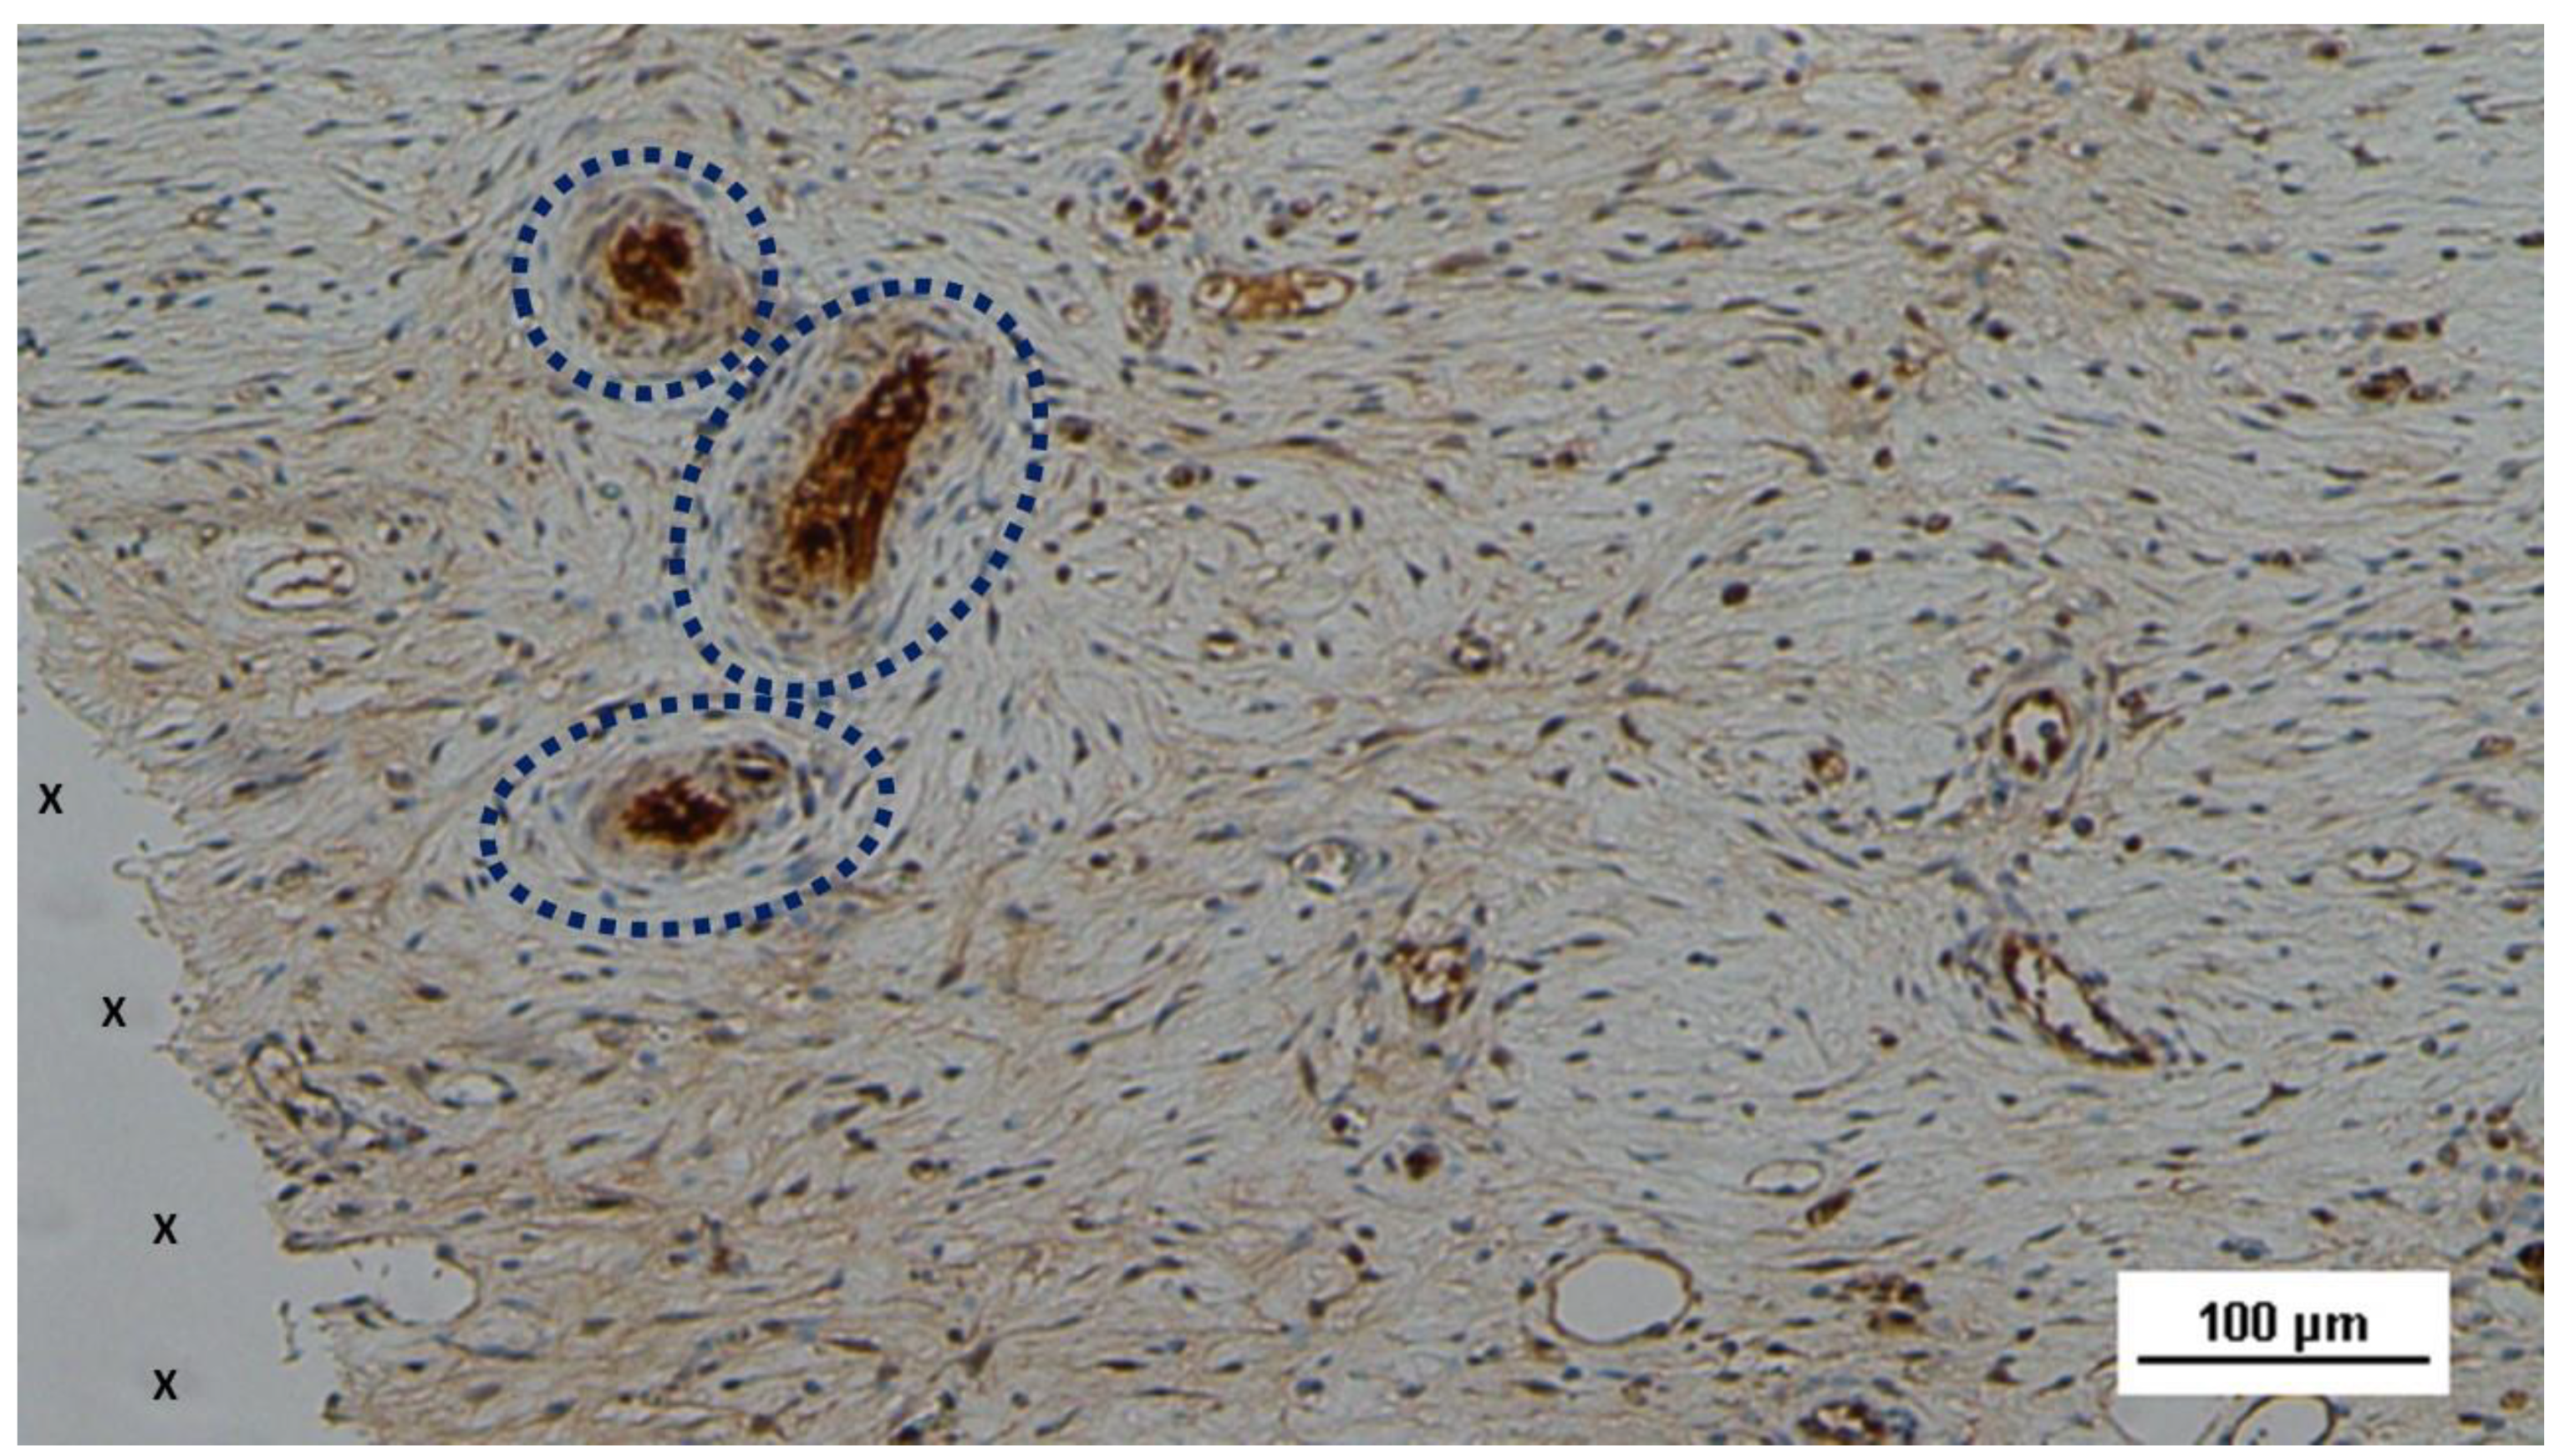

Figure 12. - Biopsy specimen excised from the 3D scaffold of the S&S device 6 months post-op: A large nervous structure (blue circle) with well-developed axons (stained brown) encased in a thick myelin sheath is shown in close proximity to the 3D scaffold of the S&S device. NSE 100X.